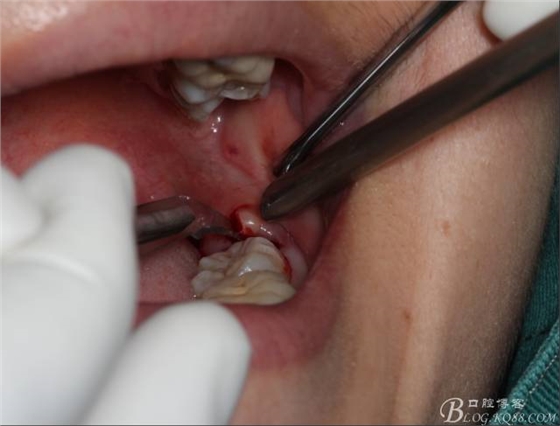

在取出阻力冠后,嘗試性看能取出全部的牙體不,就是取不出也能整體撬動(dòng)牙根。

640 (14).jpg

計(jì)劃總趕不上變化,何況是充滿變異的智齒。由于可操作空間較小,原來計(jì)劃?rùn)M向分根改成矢狀分根。

640 (15).jpg

現(xiàn)在都在提倡微創(chuàng),個(gè)人看法微創(chuàng)是相對(duì),所當(dāng)然微創(chuàng)是我們的追求。完全撥出,縫合關(guān)閉創(chuàng)口,常規(guī)智齒撥除醫(yī)囑,不適隨診。